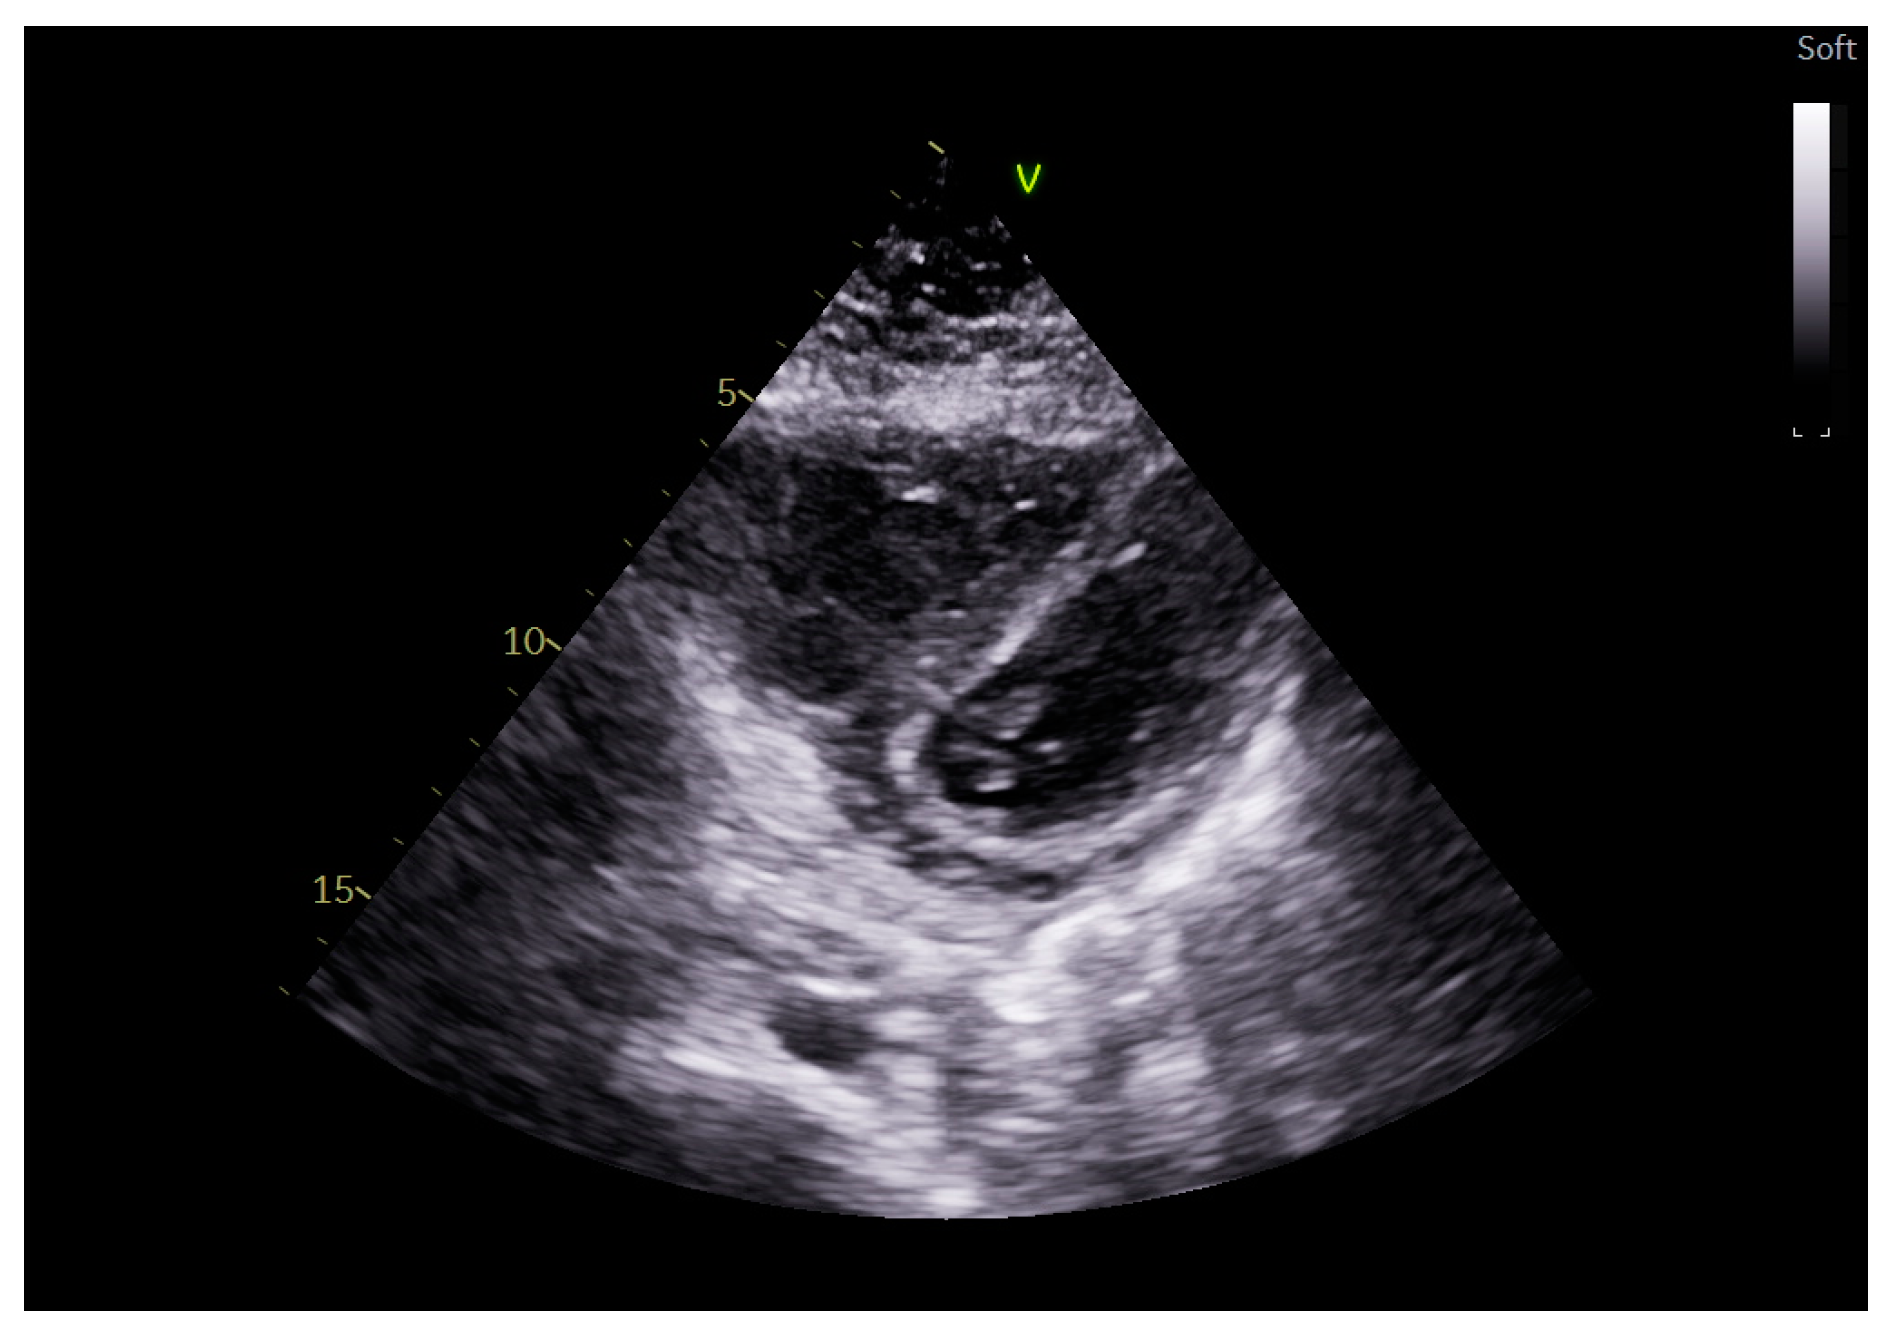

4. Echocardiographic Evaluation in Mechanical Ventilation

5. Right Ventricular Echocardiographic Evaluation